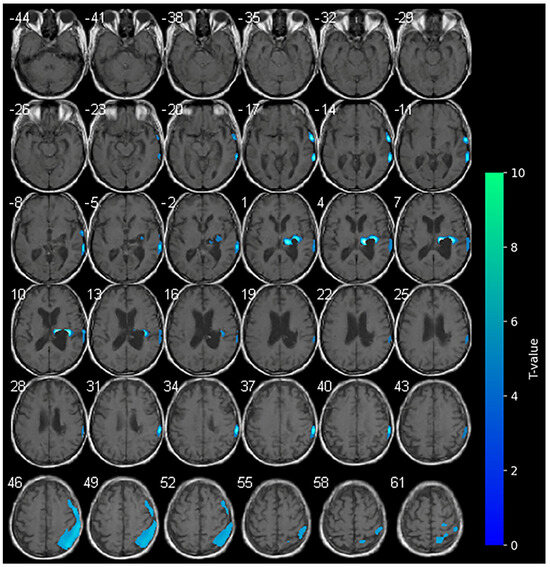

3.3. 18F-FDG-PET and Cathodal-tDCS (T2)

No variations in the marked hypometabolism were detected in the right hemorrhagic nucleo-capsular lesion. The right fronto-parietal cortex showed reduced metabolism, a condition which was not previously observed at the baseline. No areas of significantly increased metabolism were appreciable during cathodal-tDCS (Figure 3).

A clinical improvement was observed at T2. The NIHSS score decreased to 16 and the mRS improved to 4, suggesting a partial recovery of function and reduced dependency in some basic activities of daily living. Of note, motor function showed early indications of recovery, as evidenced by an increase in the MI scores to 9 for the upper limb and 18 for the lower limb. The LCF demonstrated stability at level 6, even though the responses to requested commands were consistently more suitable.

With regard to cathodal-tDCS administered on the unaffected side, brain metabolism appeared reduced in the ipsilateral hemisphere, as expected. In the occipital and frontal regions of the affected side, we observed hypoactivation that was not present at the baseline. The expected reduction in metabolism during cathodal stimulation may indicate a suppression of maladaptive hyperactivity in the local stimulated area, also resulting in a more balanced interhemispheric interaction. In addition, the PET images may reflect the patient’s progressive clinical improvements, including reductions in NIHSS and mRS scores and modest gains in motor function, particularly in the lower limb. Furthermore, the observed progressive improvement in cognitive performance may be linked to enhanced network integration with a more efficient brain network reconfiguration (cortical-subcortical) [34].

Figure 3. SPM analysis results (t-maps) at T2. The blue areas indicate voxel values of the patient that were significantly hypometabolic from the normal control group (p > 0.001).